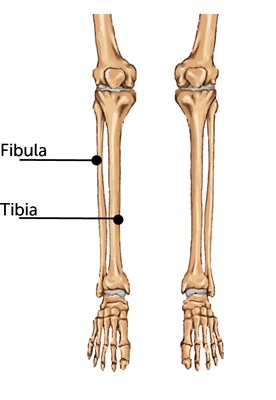

Det er den der knogle der stikker ud ved ankeln. Det heldige er at det ikke er Tibia-knoglen der støtter hele vægten når man står på foden. Så jeg kan stå på foden, men jeg kan ikke vride eller vippe med foden udan at det gører ont som ind i helvede. Alle muskler og sener der ordner balance, vridning og vipning af fode er nemlig fastgjort til Fibula-knoglen der er brækked. Det bliver svært at komme op på, og af motorcyklen, og lige så svært at skifte gear!